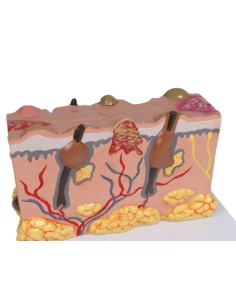

Dal cranio in 22 parti con incastri magnetici ai modelli di colonna vertebrale, da quelli di articolazioni a quelli di cuore, ogni pezzo della nostra collezione è progettato per un’immersione totale nello studio dell’anatomia umana. I nostri modelli, realizzati tramite scansioni di ossa vere, garantiscono un’esperienza tattile autentica e una fedeltà di peso quasi identica agli originali.

Essenziali per studenti e professionisti, i nostri modelli anatomici sono strumenti didattici che permettono di osservare le strutture anatomiche con precisione, eliminando la necessità di dissezioni o studi invasivi. Sono inoltre utili per spiegare ai pazienti le patologie, rendendo la comunicazione più efficace e risparmiando tempo prezioso.